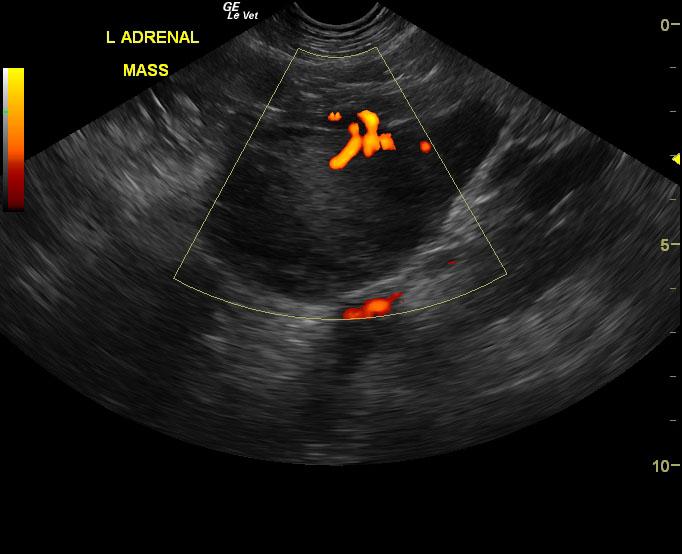

Left adrenal gland mass invading the left phrenic vein. This mass appears to be resectable and is most consistent with adrenal gland carcinoma. Surgical consultation is recommended as well as three view chest radiographs and blood pressure measurements.

The right adrenal gland was isoechoic to surrounding fat. It measured 2.1 x 0.9 cm. The left adrenal gland comprised a 7.9 x 5.3 cm strongly vascular mass noted on power flow Doppler. Invasion into the left phrenicoabdominal vein was noted. However, the vena cava was not invaded at this time.